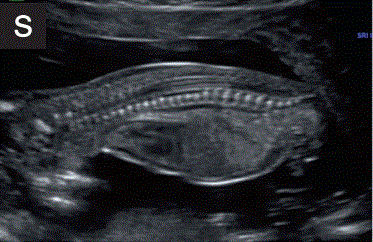

8.1如果可能的话,应在矢状切面下检查脊柱,评估椎体对齐和皮肤覆盖物的完整性(图2s)。

胎儿mt是什么检查什么疼吗【文献学习/规范指南】ISUOG实践指南(2023更新): 11-14周胎儿超声检查(全文)_https://www.jmylbn.com_新闻资讯_第26张

图2 11+0至14+0周时,可作为详细胎儿超声检查的一部分获得的解剖图。

(s)矢状面图显示胎儿脊柱从颈部到骶骨的长度。注意可见完整的皮肤覆盖物和椎体骨化,这已经开始于骶骨和腰椎和胸椎。

8.2 妊娠12周后,椎体发生骨化。

8.3 当发现任何可疑的开放性脊柱裂的颅内征象时,应特别注意脊柱的外观。